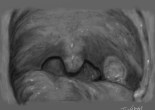

Abcès et phlegmon péri-amygdalien

Ce sont des infections de la sphère ORL avec pour point de départ une infection microbienne de la loge amygdalienne, responsable d’un syndrome infectieux local souvent intense avec un risque … Lire la suite